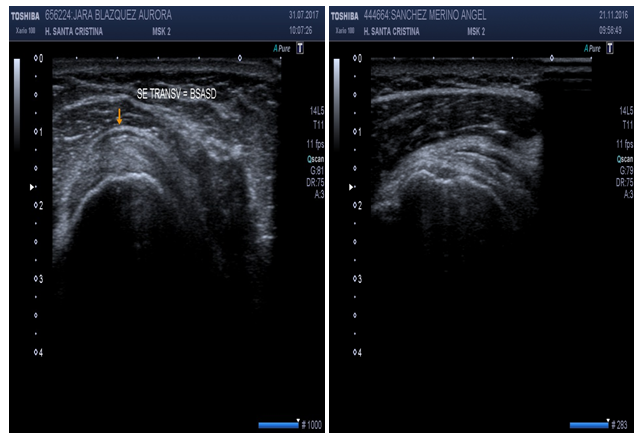

Subscapularis tendon (short axis) (Figure 5)

Patient position: Patient is seated, arm at side, elbow flexed, arm externally rotated with palm up (supination).

Probe position: Probe over anterior deltoid, axial to upper arm, short axis view.

Scan of structures: Because of the orientation of fibers, short axis depicts the insertion of tendon on lesser tuberosity and it is seen as beak-shaped.17,18

Subscapularis tendon (long axis) (Figure 6)

Probe position: Probe over anterior deltoid, longitudinal to upper arm, long axis view.

Scan of structures: Because of the orientation of fibers, longitudinal view is actually a transverse view of the muscle´s tendon. Three or four bright tendon fiber bundles may be seen on this scanning. Do not interpret as rupture or tears on subscapular tendon.17,18

Figure 5 Sonoanatomy of the subscapularis tendon (short axis).

Figure 6 Sonoanatomy of the subscapularis tendon (long axis).

Figure 17 Subacromial subdeltoid bursitis greater than 2mm.